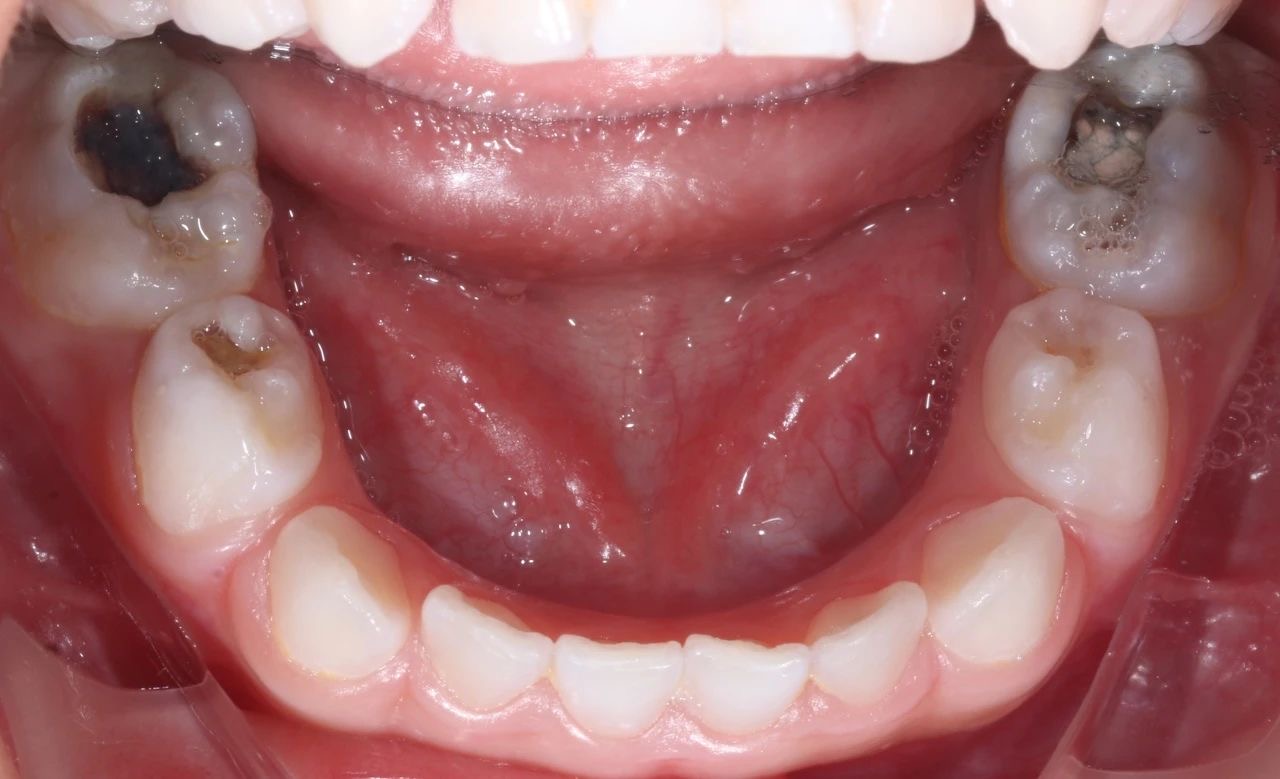

由于孩子不配合,这次就诊时,孩子在姥姥的按压下,只能接受了一小步止疼治疗。但是,从孩子的口腔情况来看,他的好几颗牙齿都龋坏得非常严重,而且其中有三颗牙甚至已经坏到了需要做根管治疗的程度。

手术过程中,口腔科的医生们和麻醉科的医生们密切配合,在很短的时间内,流畅地完成了3颗牙的根管治疗并佩戴了金属预成冠,2颗龋齿的修补,以及4颗乳牙的窝沟封闭操作。

治疗前后对比图

孩子的牙齿恢复到了正常状态,不仅解决了当下的病痛,还在很大程度上消除了未来发生蛀牙的隐患,让这个家庭重新充满了幸福和安定的气息。